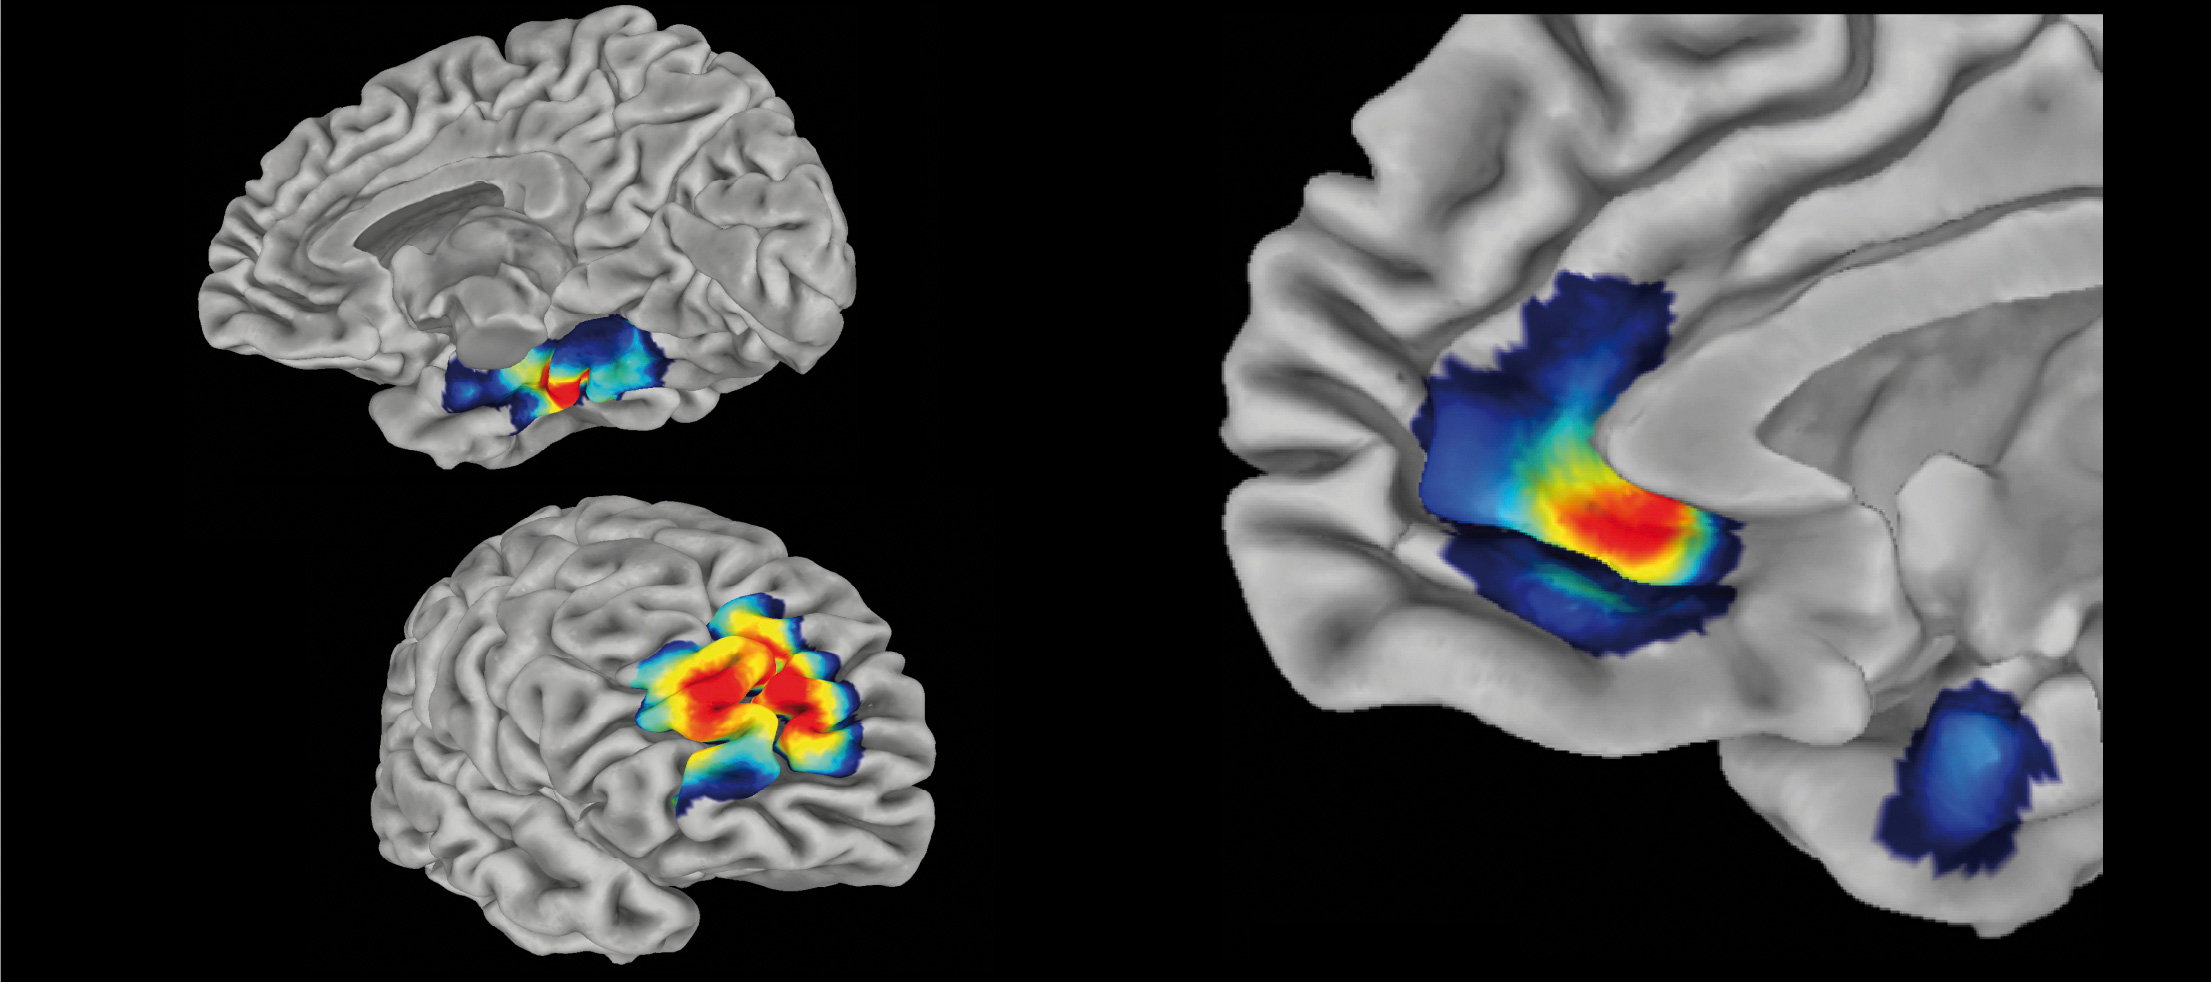

Prof. Dr. Lukas Pezawas combines psychiatric patient care with innovative cutting-edge research. After his clinical training at the Medical University of Vienna (1994–2001), he conducted research as a Postdoctoral Fellow at the National Institute of Mental Health (NIH) in Bethesda, USA (2001–2005), where he published foundational work on imaging genetics of mood disorders. His research focuses on the neurobiological mechanisms of depression, particularly the identification of fMRI biomarkers for predicting antidepressant response. Since 2005, he has led a research group at the Medical University of Vienna. A visiting professorship at Stanford University (2015) expanded his expertise in the field of digital interventions. Currently, his focus is on the development and clinical evaluation of Digital Health Applications (DiGAs) as well as the systematic investigation of treatment-resistant depression within the Vienna TRD Registry.

- Prediction of Antidepressant Response Using fMRI

Fig1